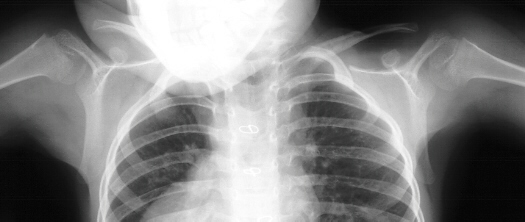

This is a 5 year and 3 month old white female was the product

of a full-term normal spontaneous vaginal delivery with a diagnosis

of CHARGE syndrome (defects of the eyes, ears, heart, choanal

atresia (primordal oronasal opening into the brain, mental retardation,

and genital hypoplasia). She presented for evaluation of a webbed

neck, left side worse than right. The child has developmental

delay and began walking at 4 years of age. She had undergone previous

surgery for strabismus and an atrial septal defect. Physical exam

revealed defects of the eyes and ears, the neck was shortened

and webbed (left worse than right). The back, shoulders and scapula

were elevated (left worse than right). The scapula was rotated

down and away from spine. Shoulder abduction was 110 degrees on

right and 100 degrees on left.